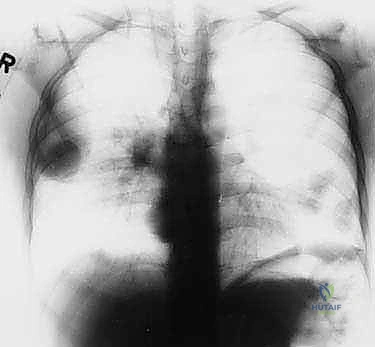

تختلف الأورام في سلوكها البيولوجي بشكل جذري. الأورام الحميدة، رغم أنها قد تسبب ألماً أو تضغط على الأعصاب المجاورة، إلا أنها لا تنتشر إلى أعضاء أخرى. أما الأورام الخبيثة (مثل الساركوما العظمية Osteosarcoma، ساركوما إيوينغ Ewing's Sarcoma، أو الساركوما الغضروفية Chondrosarcoma)، فلها قدرة تدميرية موضعية عالية وقابلية للانتشار (الانبثاث) إلى الرئتين أو عظام أخرى.

- الأشعة المقطعية (CT Scan): ضرورية لتقييم القشرة العظمية والتكلسات داخل الورم، وللبحث عن أي انتشار في الرئتين.

- إذا كان الورم خبيثاً (ساركوما): يتم وضع خطة علاجية شاملة (Multidisciplinary approach) قد تتضمن العلاج الكيميائي، العلاج الإشعاعي، والجراحة الكبرى لاستئصال الورم مع الحفاظ على الطرف (Limb Salvage Surgery).